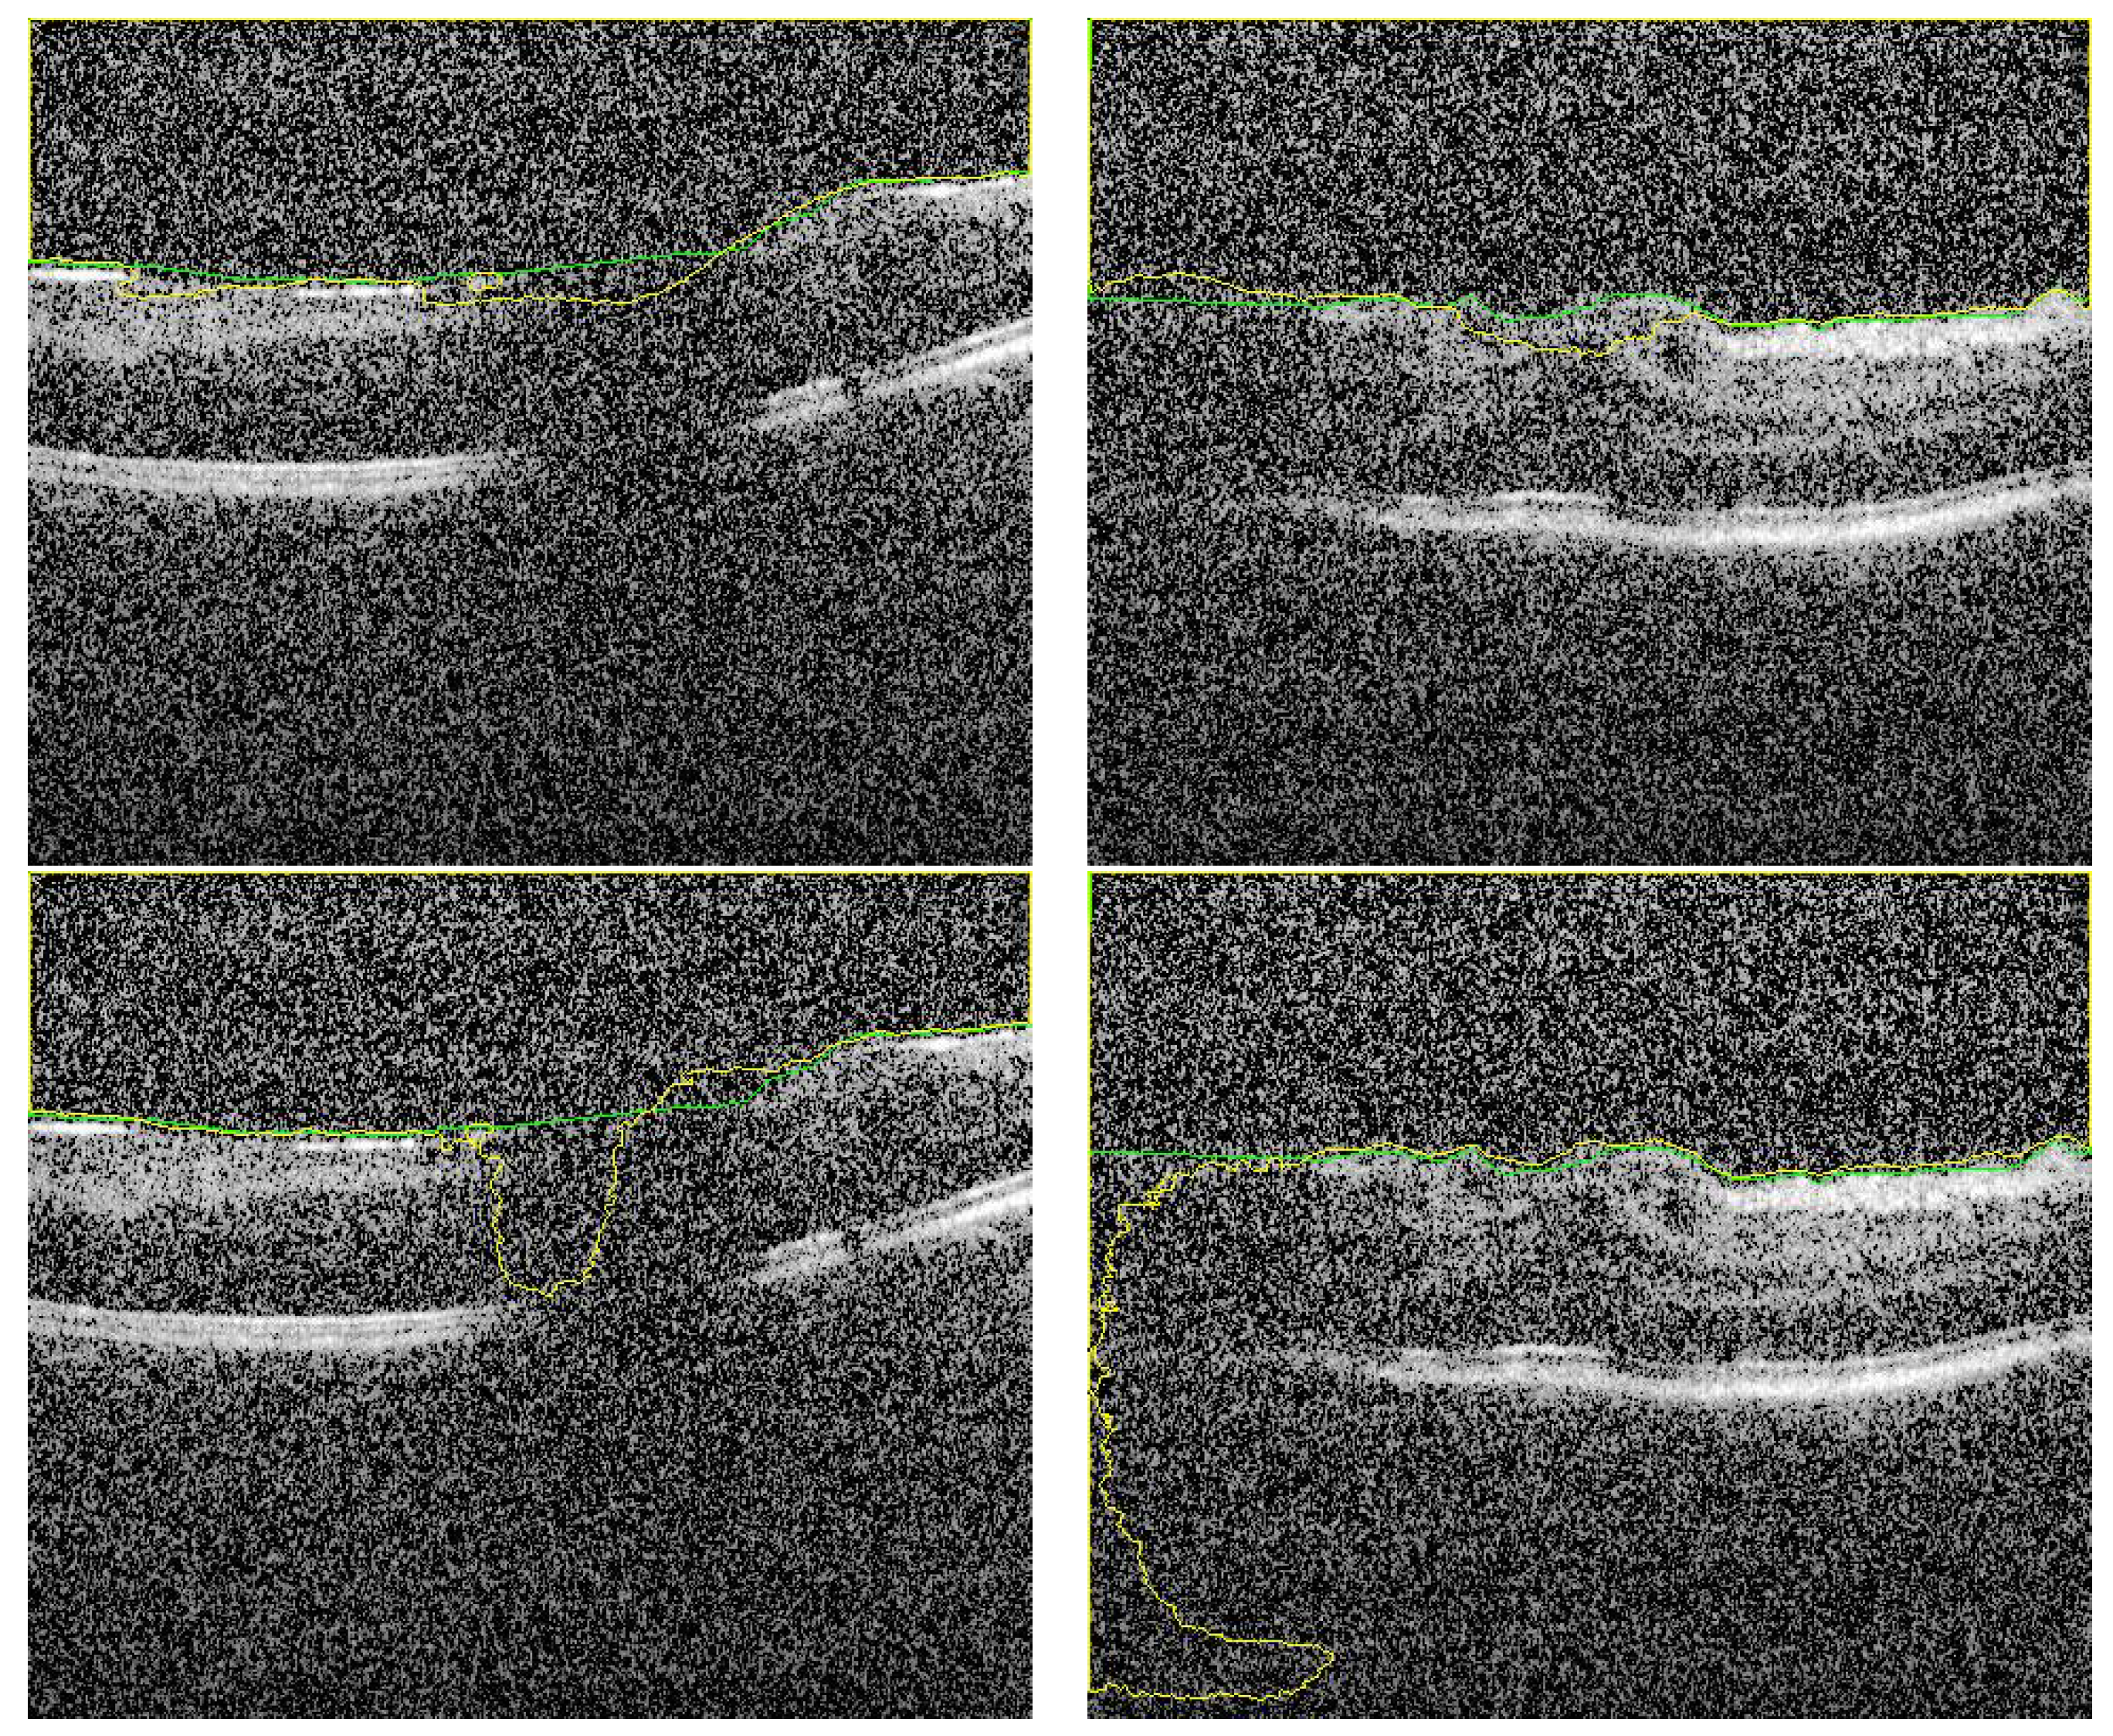

To demonstrate the accuracy of our approach in the segmentation stage, some representative results are presented in Figure 5 and Figure 6. As demonstrated in from Figure 5, it can be readily seen that the segmentation results have very high accuracy (DC = 0.99) despite the variations in vitreous inflammation degree, which is related to the contrast of the image. In the first row of Figure 5, the image is clear and the contrast between the object and non-object regions is easily spreadable. Although, in the second row, the image has low contrast, the accuracy of the segmentation is nearly the same as that of the first row.

Figure 5.

Sample of high accuracy segmentation. The first row represents grayscale images with high contrast, and the second row represents low contrast images with higher degree of vitreous inflammation. Green and yellow colors represents the ground truth and the CNN segmented respectively.

Figure 6.

Sample of segmented images of our proposed approach (first row) compared with previous results using only U-Net [16] (second row). The green and yellow colors represents the ground truth and the CNN-segmented respectively.

Despite the fact that the selected images in Figure 6 (first row) have low contrast with high similarity between object and non-object regions, our approach has succeeded to segment the vitreous region with high accuracy. The DC for these images ranges from 0.961 to 0.978, which is acceptable but lower accuracy compared to the group of images in Figure 5. However, by visual inspection, the difference between the ground truth (yellow contour) and our system segmentation (green contour) in the first row of Figure 6 is not significant because the region in the middle of the retina is completely unclear. So, the difference between the two contours in the middle region is just a difference between the interpolation capability of two different techniques trying to predict the unclear region. The second row in Figure 6 contains the same images in the first row that with contours resulted from the previous technique. Also, we can confirm that, the high noise in the presented images proves the high efficiency of the proposed technique. Adaptive shape model has highly succeeded to reduce the effect of this noise by selecting proper values of and/or the sliding window size.